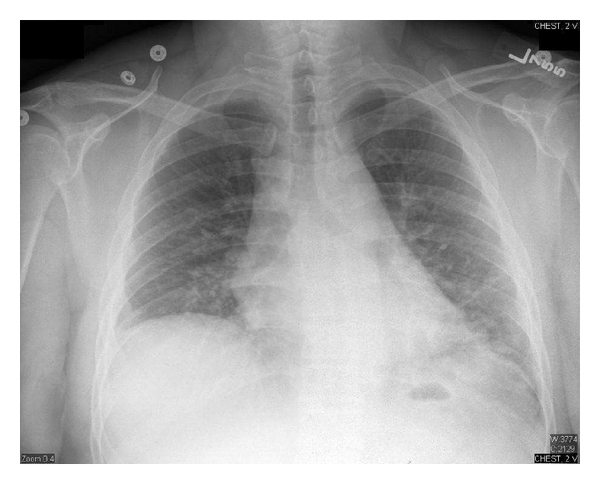

A 42-year-old male with acute myeloblastic leukemia (FAB classification AML M2, WHO classification: AML with recurrent genetic abnormalities: t (8 : 21)) received induction chemotherapy with cytarabine and idarubicin twice (he did not achieve remission with the first induction) followed by consolidation with high-dose cytarabine. He received three cycles of high-dose cytarabine without incident. He was admitted to receive his fourth cycle and did well until fourteen days after chemotherapy when he developed neutropenic fever. His maximum temperature was 40.1°C, his total white blood cell count was less than 100 cells/μL, blood cultures were drawn, and a chest X-ray was done (Figure 1). He was started on piperacillin/tazobactam and vancomycin. The next day, the two blood culture sets grew Gram-positive cocci in chains which were identified later to be streptococcus viridans. The same day, he became hypotensive and hypoxic (he required 100% FiO2 by nonrebreathing mask to maintain SpO2 above 95%), he was transferred to the intensive care unit for septic shock and acute hypoxic respiratory failure, and he required vasopressors and intubation for mechanical ventilation. Patient was started on caspofungin.

Eighteen days after chemotherapy, the day of recovery of neutropenia, his CXR showed significant worsening with bilateral infiltrates (Figure 2), his fever trended up, and his mechanical ventilation settings (FiO2 and PEEP) increased, he developed acute respiratory distress syndrome (his PaO2/FiO2 was less than 200 with bilateral infiltrates on CXR). Over the following three days, he continued to deteriorate clinically and CXR was getting worse (Figure 3) despite being on appropriate antibiotics and without an evidence of a new infection. Granulocyte colony-stimulating factor (GCSF) was discontinued when the absolute neutrophilic count reached 8000 cell/μL. A transthoracic echocardiogram did not show an evidence of heart failure or valvular vegetation.